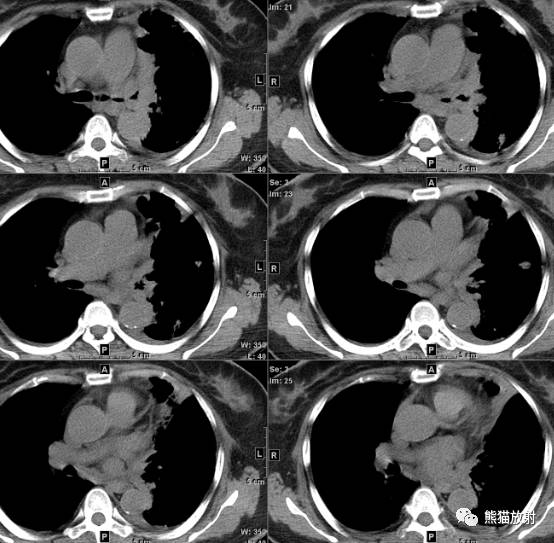

纵隔窗(平扫 增强)

在我院行胸部CT平扫(下图):

左主支气管不规则狭窄,腔内可见小结节样等密度灶;左肺阻塞性肺不张,多发炎性改变表现,纵隔多发增大淋巴结,依然不得不把中央型肺癌放在第一诊断,建议纤支镜检查。 医学百科网 | YxBaike.Com